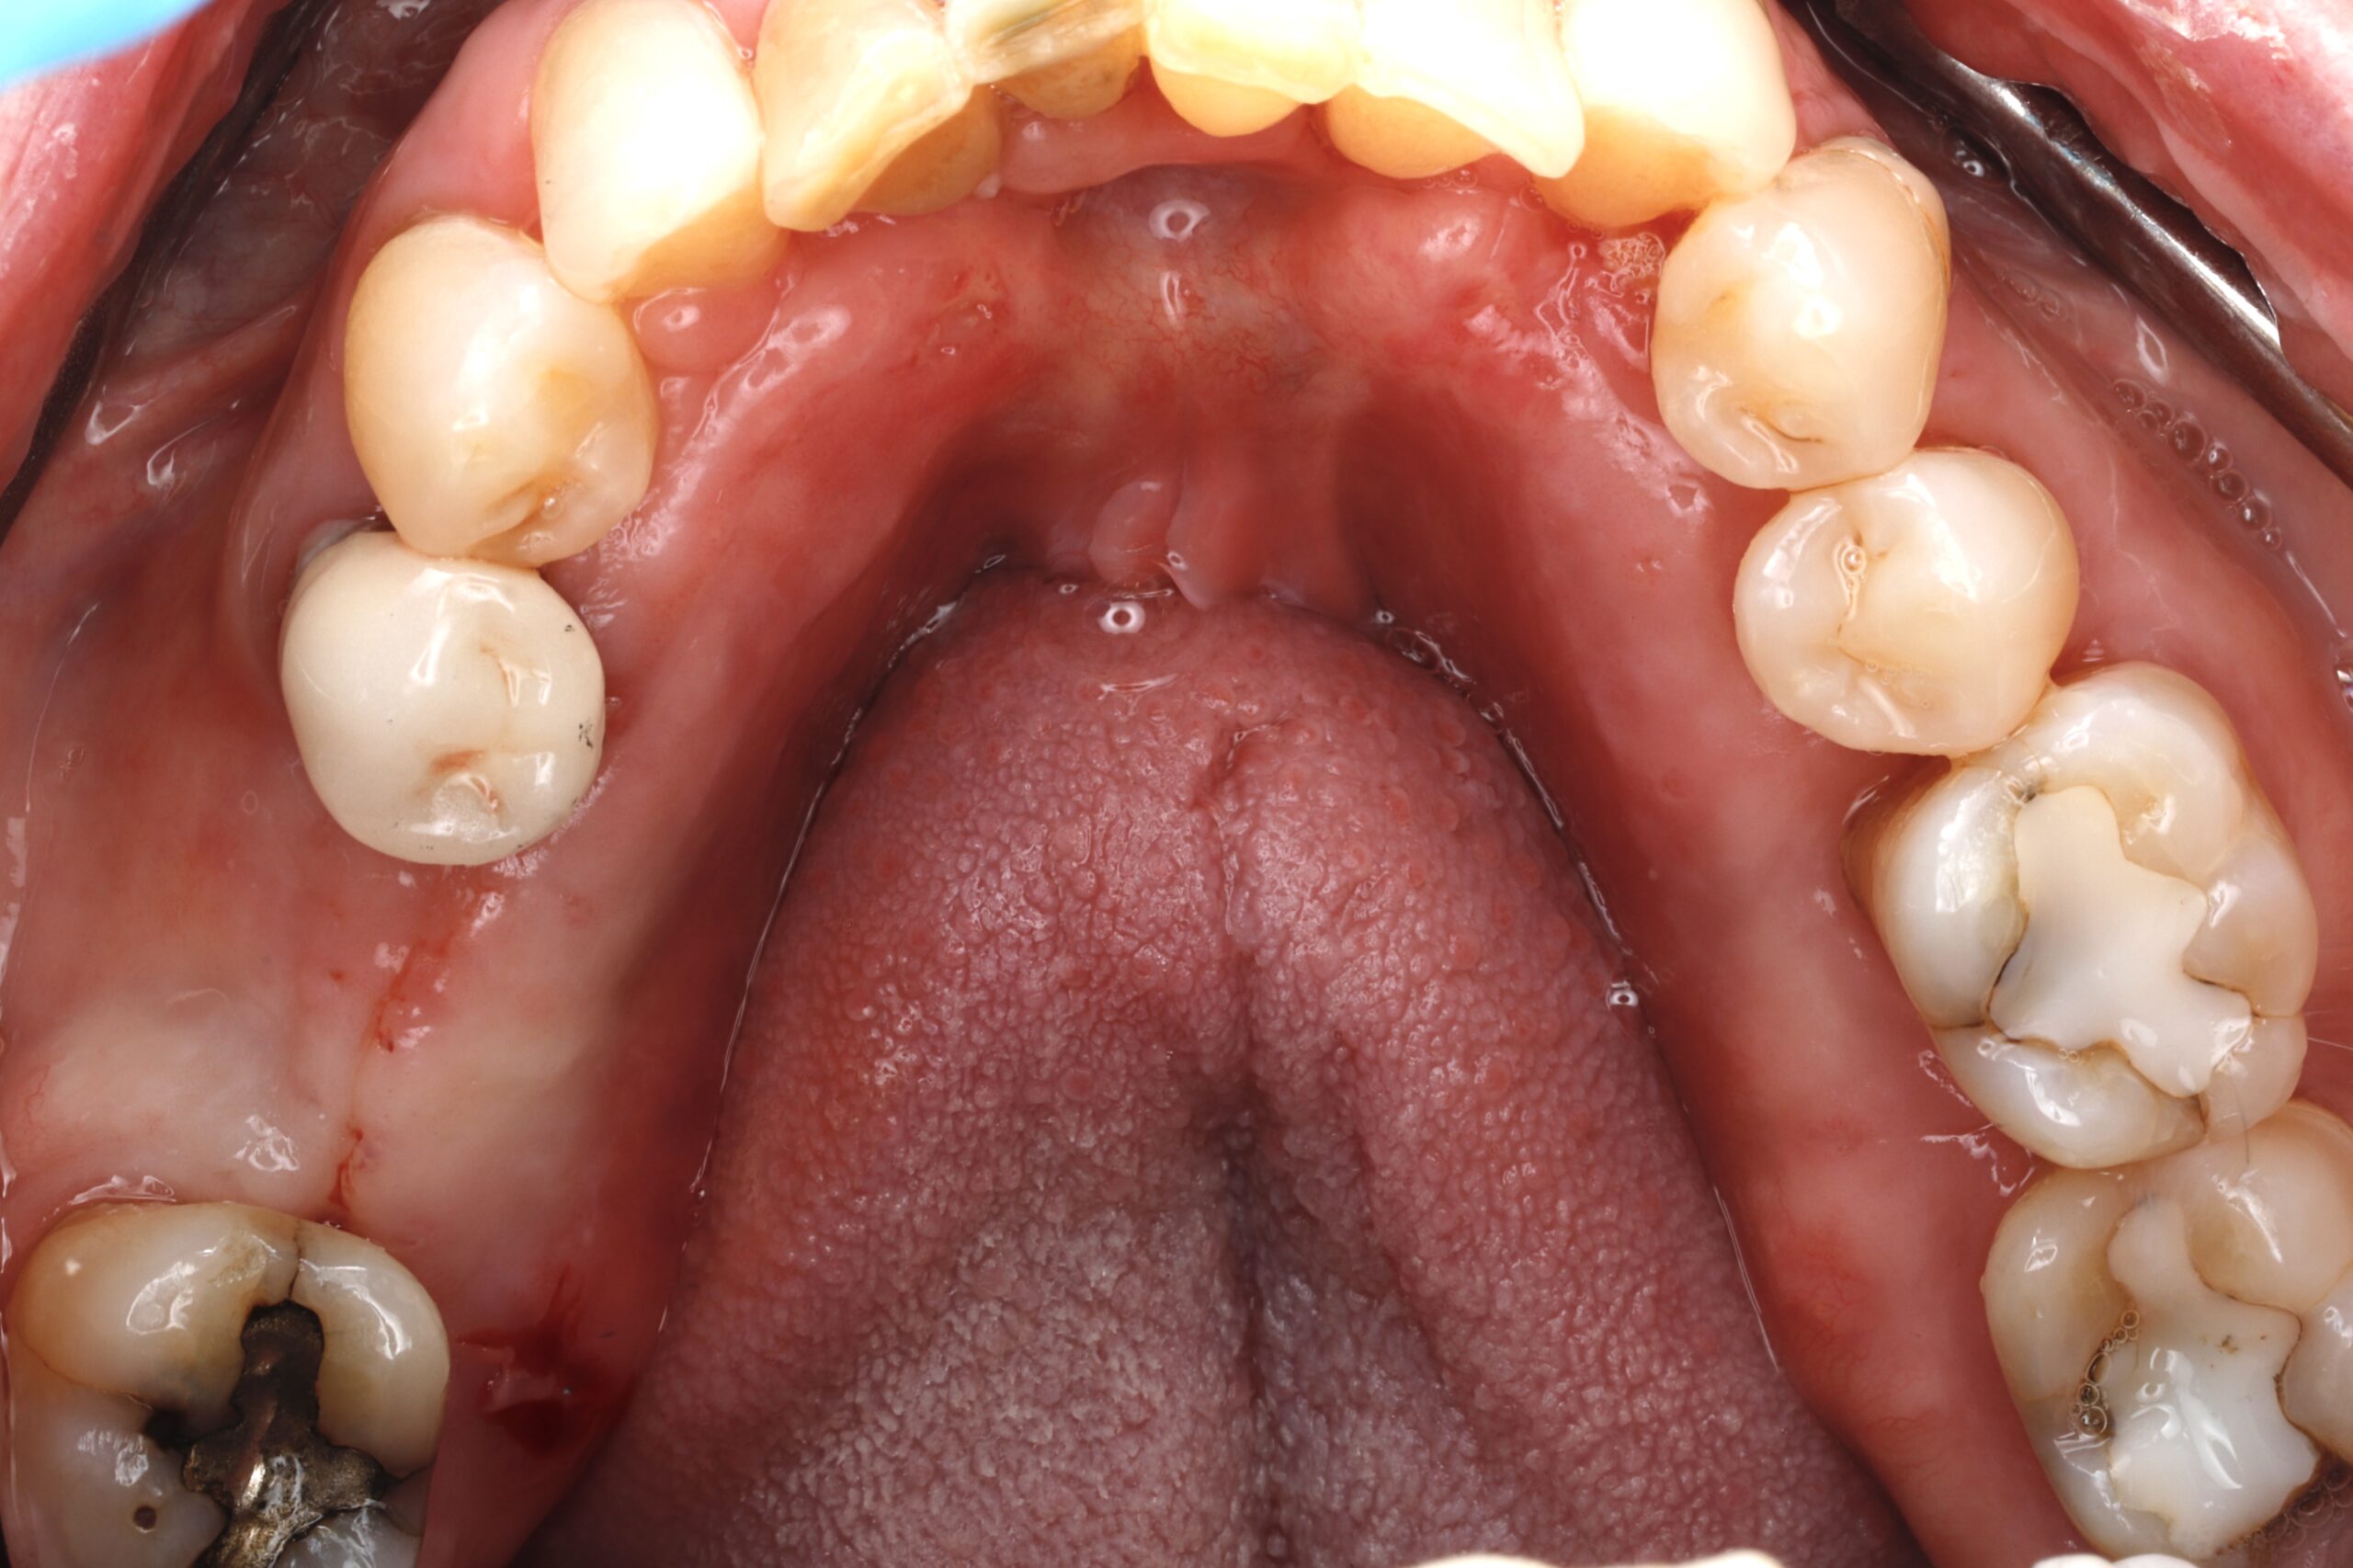

Before

After